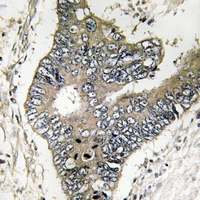

IHC (Immunohiostchemistry)

(Dilution: WB: (1/500 - 1/1000), IH (1/50 - 1/200)Immunohistochemical analysis of GUF1 staining in human colon cancer formalin fixed paraffin embedded tissue section. The section was pre-treated using heat mediated antigen retrieval with sodium citrate buffer (pH 6.0). The section was then incubated with the antibody at room temperature and detected using an HRP conjugated compact polymer system. DAB was used as the chromogen. The section was then counterstained with haematoxylin and mounted with DPX.)